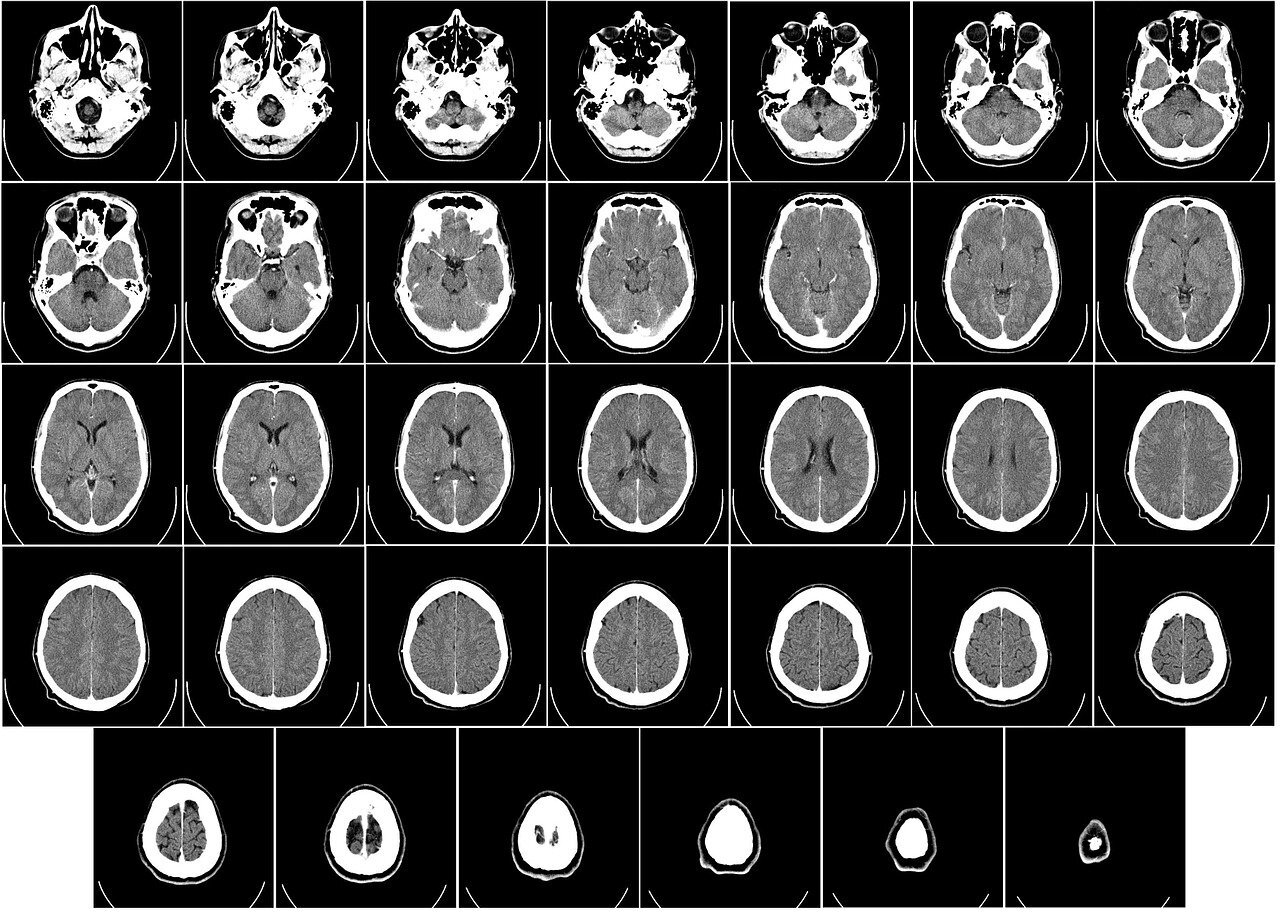

뇌경색은 발생 후 얼마나 빨리 치료를 시작하냐에 따라 예후가 결정됩니다. 증상이 발생하면 최대한 빨리 병원을 방문하여 초급성기 치료를 받아야 합니다.

급성기 치료 후에는 원인에 따라 재발 방지를 위한 치료를 하게 되며 후유증에 대한 재활치료도 가능한 한 빨리 시행하는 것이 회복에 도움이 됩니다.

증상이 처음 나타난 후 4-5시간이 경과하지 않았다면 주사 제제를 통한 혈전용해술을 시도해 볼 수 있습니다.

24시간이 경과하지 않았고 대뇌혈관이 막힌 것을 확인하였다면 막힌 혈관에 대해 기계적 재개통술을 시도할 수 있습니다.

초급성기가 경과한 후에는 보전적 치료를 시행합니다.

혈전용해제, 항혈소판제, 항응고제 등을 사용하여 재발 방지를 위한 약물치료를 시행합니다. 약물요법만으로 안될 때 스텐트 삽입술이나 경동맥 내막 절제술을 시행하기도 합니다.